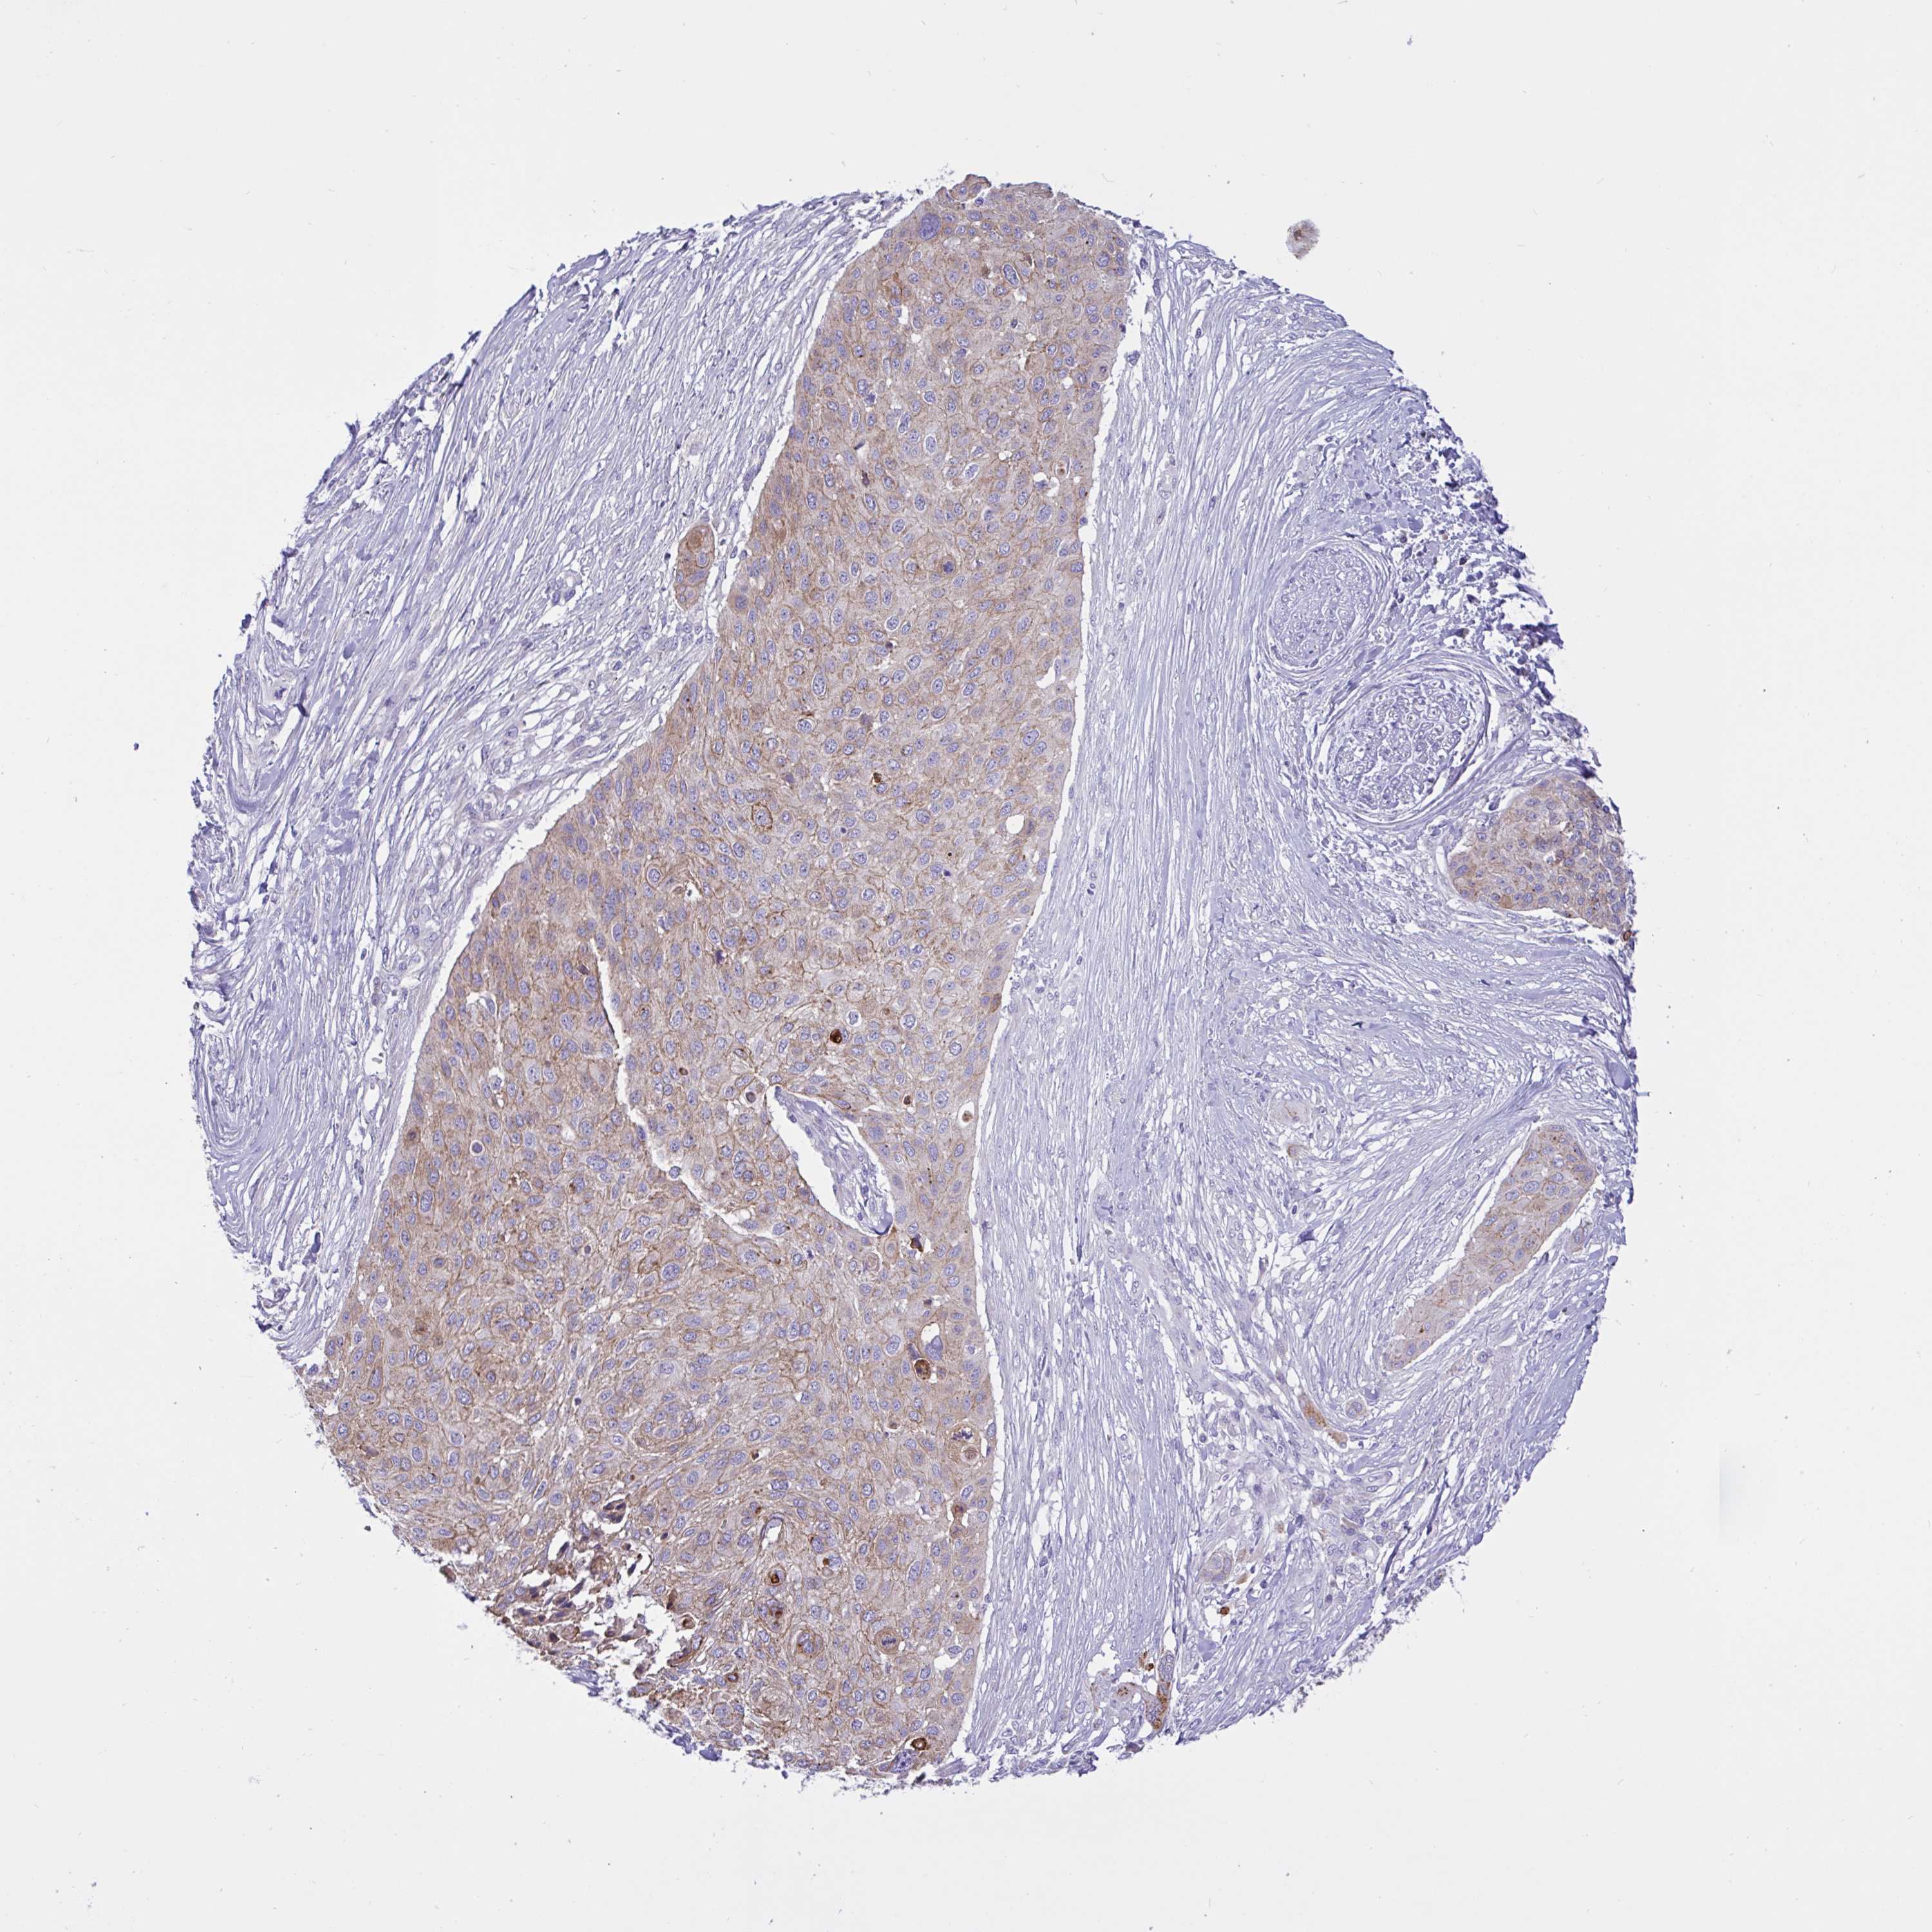

CANCER SKIN CANCER Show tissue menu

Basal cell and squamous cell cancer

SKIN CANCER - Protein expressioni

A mouse-over function shows sample information and annotation data. Click on an image to view it in a full screen mode. Samples can be filtered based on level of antibody staining by selecting one or several of the following categories: high, medium, low and not detected. The assay and annotation is described here.

Each image is clickable and will lead to virtual microscopy that enables deeper exploration of all samples and also displays staining intensity scores, fraction scores and subcellular localization as well as patient and tissue information for each sample.

Antibody HPA049265

Antibody CAB037328

Staining

High

Medium

Low

Not detected

Intensity

Strong

Moderate

Weak

Negative

Quantity

>75%

75%-25%

<25%

None

Location

Nuclear

Cytoplasmic/membranous

Cytoplasmic/membranous,nuclear

Basal cell carcinoma

Squamous cell carcinoma, NOS

Squamous cell carcinoma, metastatic, NOS